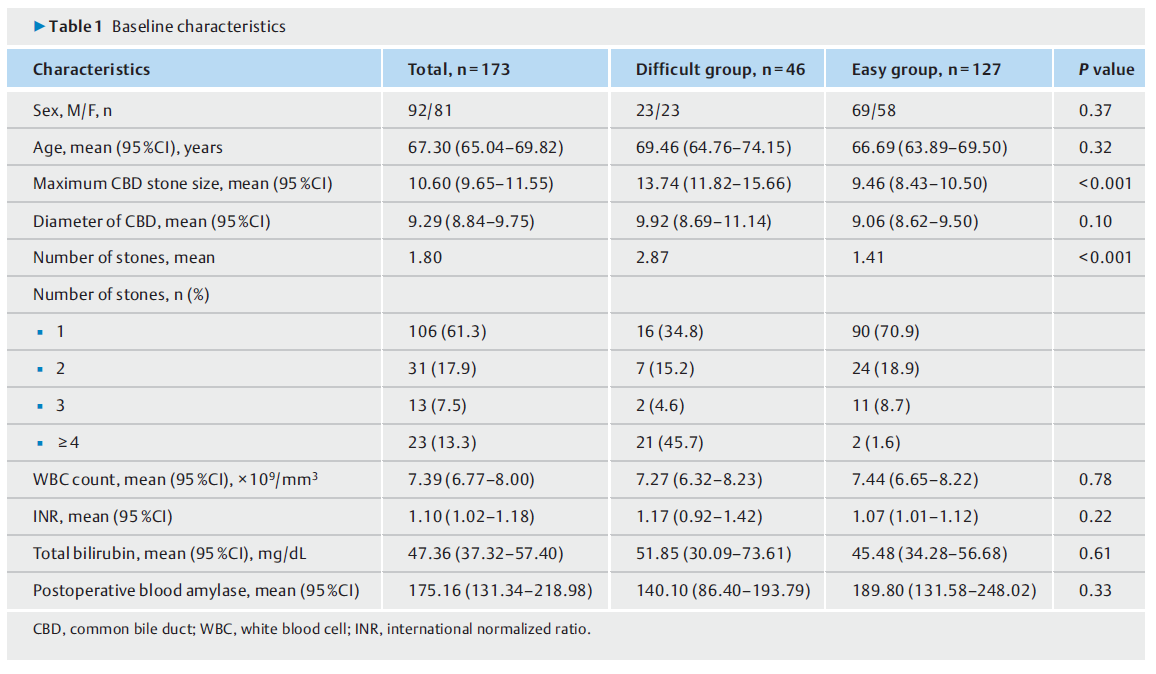

在2020年9月1日至2021年6月15日期间,共从三家医院招募了231名CBD结石患者。其中,173人符合纳入标准。共有58名患者被排除在外,原因如(图3)所示。患者队列的特征如(表1)所示。总共有46名评分为0或1的患者被计算机辅助设计系统归类为困难组,127名评分为2或以上的患者被归类为容易组。图1显示了两组的四个典型图像。

表1. 患者队列的特征